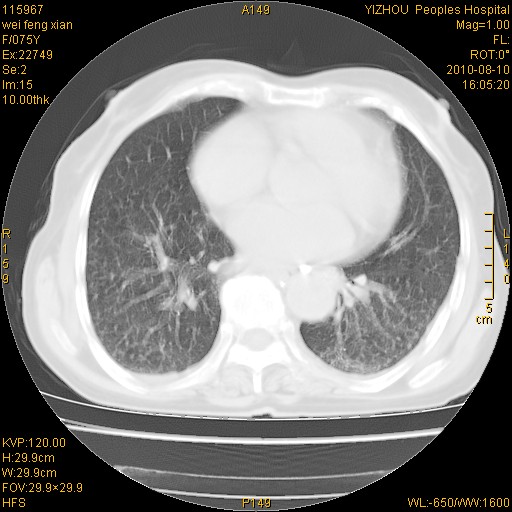

标题: CT28313:两肺弥漫性病变 [打印本页]

标题: CT28313:两肺弥漫性病变

女,75岁,患者反复头昏乏力面色苍白3年,再发10天入院。临床贫血查因。

双肺间质增生并右肺上叶炎性改变,不除外右肺上叶结核病肺内播散

考虑慢支伴右上肺慢性感染可能性大,建议结合临床排外尘肺可能。

考虑尘肺可能性大.

考虑右肺上叶炎症合并双肺结核可能性大,建议上传纵隔窗ct图片。

如果患者是男性首先考虑尘肺,但现在即是是女性也要询问职业病史。

双肺结核可能性大

考虑尘肺并结核;右上肺支气管扩张!

结核、尘肺、支气管肺泡癌都不能除外

右肺上叶继发性肺结核伴肺内血型播散!

考虑右肺上叶继发性肺结核伴两肺播散。